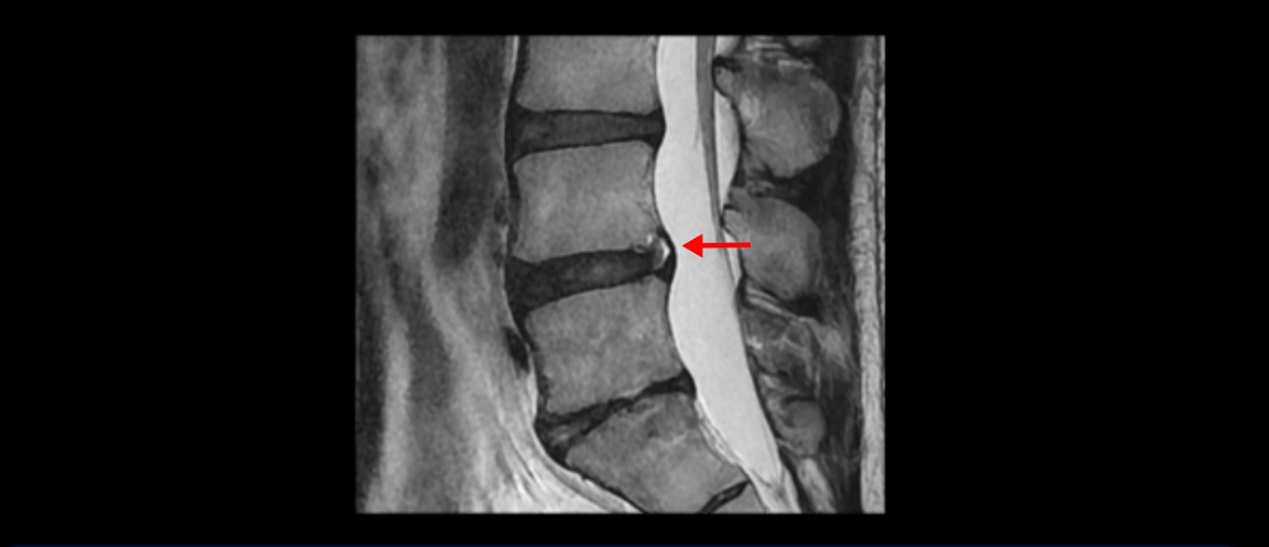

우선 이분 MRI를 보면 허리 모든 마디의 디스크가 퇴행되어 있고

여러 마디의 디스크가 조금씩 밀려나와 보이고, 디스크 섬유륜도 찢어져 보이는 마디도 보입니다.

그런데 이분의 증상과 MRI가 전혀 일치하지 않는데, 왜 그런지 지금부터 자세히 설명드립니다. 이분 증상은 앉으면 엉치와 허리가 심하게 아파 10분 이상 앉는 게 어렵고 양쪽 발가락이 앉아있을 때나 누워있을 때 다 저립니다. 걸을 때도 아파서 10분 걷기도 어렵습니다. MRI를 마디마디 살펴보면 1번 2번은 오른쪽으로 살짝 밀려나온 디스크가 있지만 전혀 심하지 않고, 뒤에 또 설명하겠지만 최근에 밀려나온 급성 디스크가 아니고 오래된 디스크로 판단됩니다.

4번 5번은 가운데로 섬유륜이 찢어져서 디스크가 살짝 밀려나와 있지만 역시나 최근에 찢어지고 밀려나온 걸로 판단되지 않고 오래 전에 찢어진 흔적으로 보입니다.

5번 1번 역시 가운데로 디스크 조금 밀려 나와있지만 신경 공간 넓이는 아주 넓어서 신경 눌림 있을 거라고 예상이 안됩니다.

추간공도 보시다시피 왼쪽, 오른쪽 전부 다 매우 넓어서 신경이 눌릴만한 부분이 전혀 보이지 않습니다.

이분은 어떤 한 병원에서 디스크 내장증 얘기를 들으셨는데요. 여기 보시는 것처럼 4번 5번의 하얀 HIZ(High Intensity Zone)을 보고 디스크 내장증의 근거로 얘기하는 병원들이 있는데,

이 HIZ는 섬유륜이 찢어졌다가 이미 아문 뒤에도 얼마든지 보일 수 있는 흔적일 가능성이 있어서 재채기를 하면 아픈지, 허리를 구부릴 때 날카로운 통증이 생기는가 등의 증상으로 구별해야 하는데 MRI만 보고 HIZ가 보이면 그게 마치 통증의 원인인 것처럼 얘기하는 의사들이 있습니다. 이분 MRI를 자세히 보고 증상을 정말 자세히 들어본 의사가 있었더라면 다른 환자분들처럼 증상과 MRI가 일치하지 않는다는 얘기를 들을 수 있었을 텐데 이분은 그런 얘기는 듣지 못했습니다.